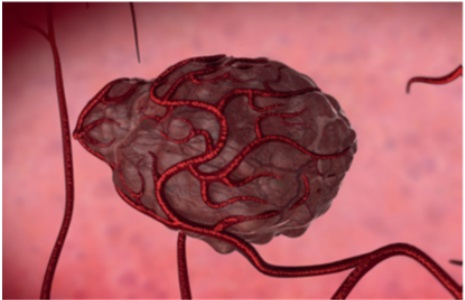

How Do Tumors Develop?

The term "cancer" applies to many diseases that occur when the cells of the body multiply in an uncontrolled manner, grow into solid tissue lumps and invade healthy tissues.